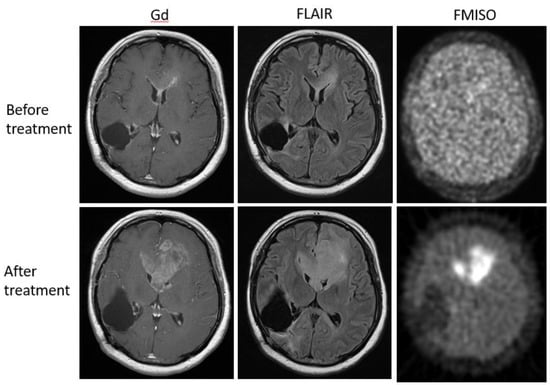

Figure 7. A 36-year-old patient with glioblastoma showed no FMISO uptake before the bevacizumab treatment (upper row). After the treatment, the patient presented with the enlarged tumor in the bilateral frontal lobe (lower row). The tumor showed high FMISO uptake. This patient was considered a ‘non-responder’.

Bevacizumab is a recombinant humanized monoclonal antibody that blocks angiogenesis by inhibiting vascular endothelial growth factor A (VEGF-A) [58]. Although bevacizumab failed to prolong the overall survival of patients with primary glioblastoma [59,60], it was effective in some populations of recurrent glioma patients. In our retrospective study, we investigated whether FMISO PET has the potential to distinguish responders to bevacizumab from non-responders [61]. Eighteen patients with recurrent glioma underwent bevacizumab treatment. We compared the patients’ pre-and post-MRI and FMISO PET to classify them as (1) MRI-FMISO double responders (n = 9, Figure 5), (2) MRI-only responders (n = 5, Figure 6), and (3) non-responders (n = 4, Figure 7). There were no FMISO-only responders. The survival analysis demonstrated that the MRI-FMISO double responders had significantly longer overall survival than the other patients, whereas no significant difference was observed between the MRI-only responders and the non-responders. We thus concluded that recurrent gliomas with decreasing FMISO accumulation after short-term bevacizumab application could derive a survival benefit from the treatment.